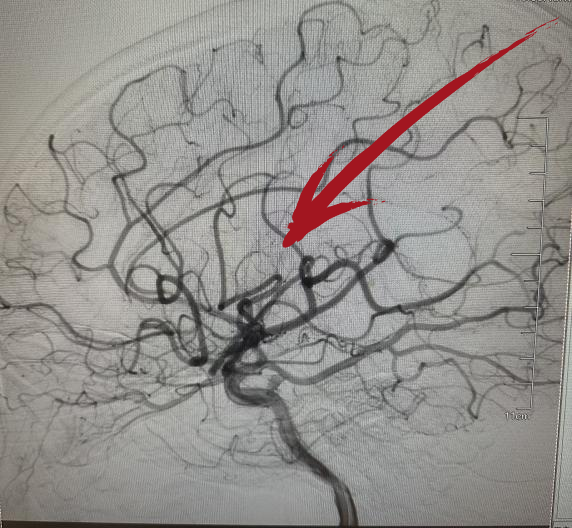

▲术后DSA提示右侧大脑中动脉已开通

从患者到院到穿刺成功仅耗时50分钟,到血管开通耗时100分钟,术后,患者肢体瘫痪及言语不利明显好转。